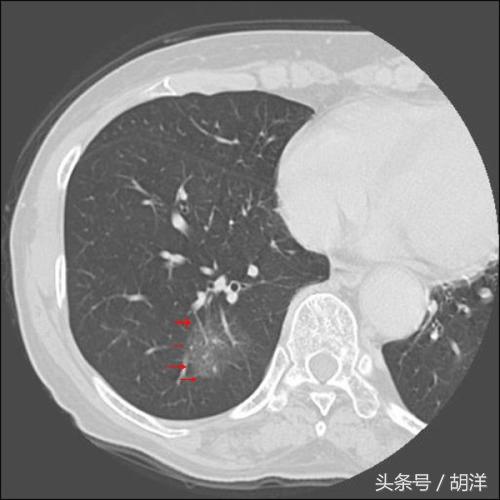

肺上发现孤立的纯磨玻璃小结节

不管什么情况下比如体检或者检查其他疾病时做胸部CT发现肺部有孤立的磨玻璃小结节时要当心,这个小结节越大越危险,这时候可以不考虑年龄,性别,是否抽烟等情况,特别是发生于下肺,恶性的可能性很大。